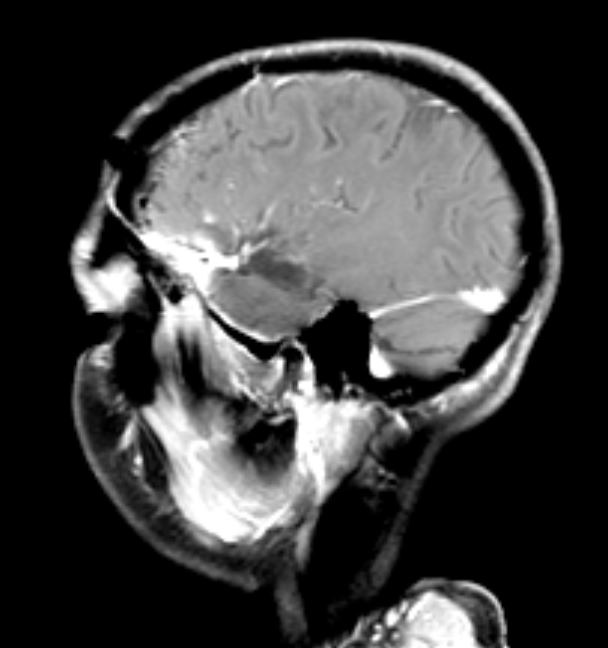

Η μετεγχειρητική μαγνητική τομογραφία ανέδειξε πλήρη εξαίρεση του όγκου.

Η μετεγχειρητική πορεία της ασθενούς ήταν ανεπίπλεκτη με και η ασθενής εξήλθε την 4η μετεγχειρητική ημέρα.